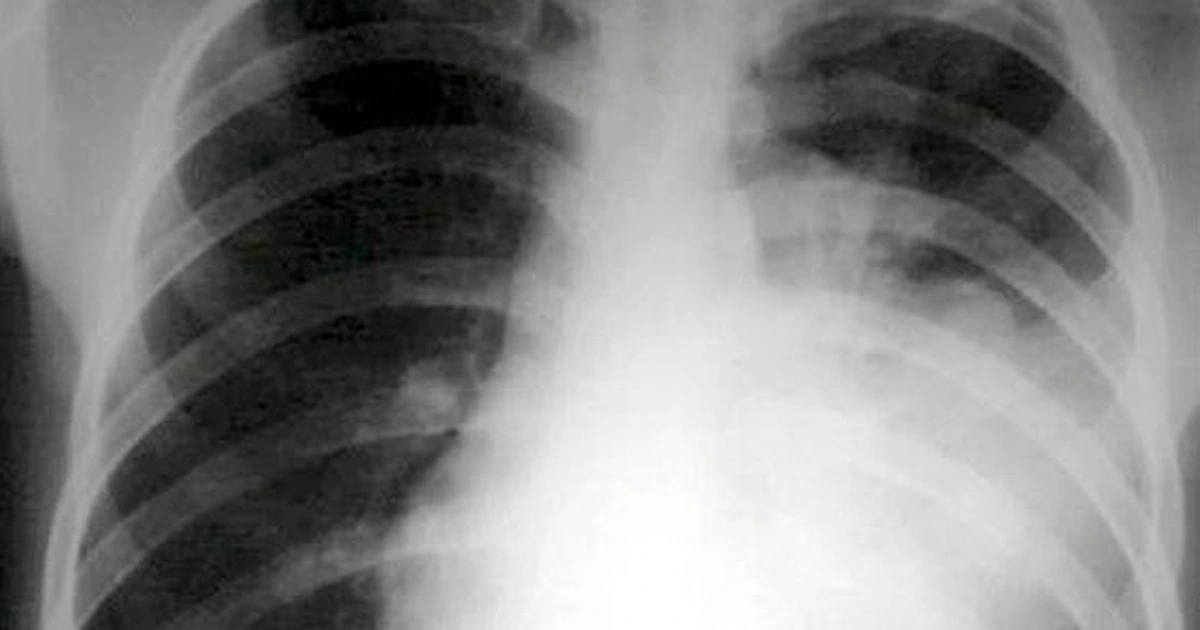

Theo Bộ Y tế, phế cầu là vi khuẩn có tên Streptococcus pneumoniae, là nguyên nhân thường gặp gây viêm phổi cộng đồng (viêm phổi bên ngoài bệnh viện), do sự phát triển quá mức của vi sinh vật gây bệnh trong nhu mô phổi, viêm và sản xuất dịch tiết trong phế nang gây "đông đặc phế nang", có thể gây tổn thương nhiều thùy khi vi khuẩn theo dịch viêm lan đến thùy phổi khác theo đường phế quản.